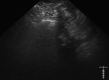

Results: Five patients (2 male, age 44-89 years) were included. Four patients had postoperative PFCs, and 1 presented with a pelvic abscess complicating acute diverticulitis. Two of 5 had fecal diversion; the remaining 3 had unaltered large-bowel anatomy. One case had a concomitant abdominal collection, treated with percutaneous drainage in the same session. An electrocautery-enhanced LAMS delivery system (15 × 10 mm) was used in all cases. EUS-TRD was performed with the direct-puncture technique and lasted less than 10 minutes in 4 cases; in the remaining case, needle puncture and LAMS placement over a guidewire was required, and the procedure length was 14 minutes. The clinical success rate was 100%. LAMSs were removed after a median of 14 (range, 12-24) days. One patient reported partial proximal LAMS migration after 24 days (mild adverse event). No PFC recurrence was observed.